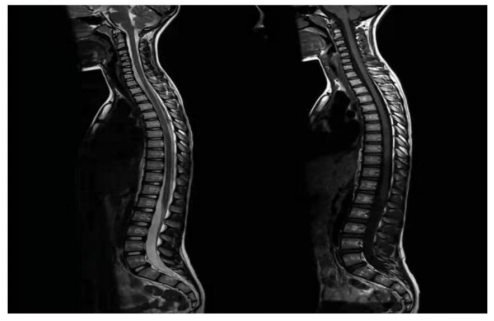

脊柱脊髓成像